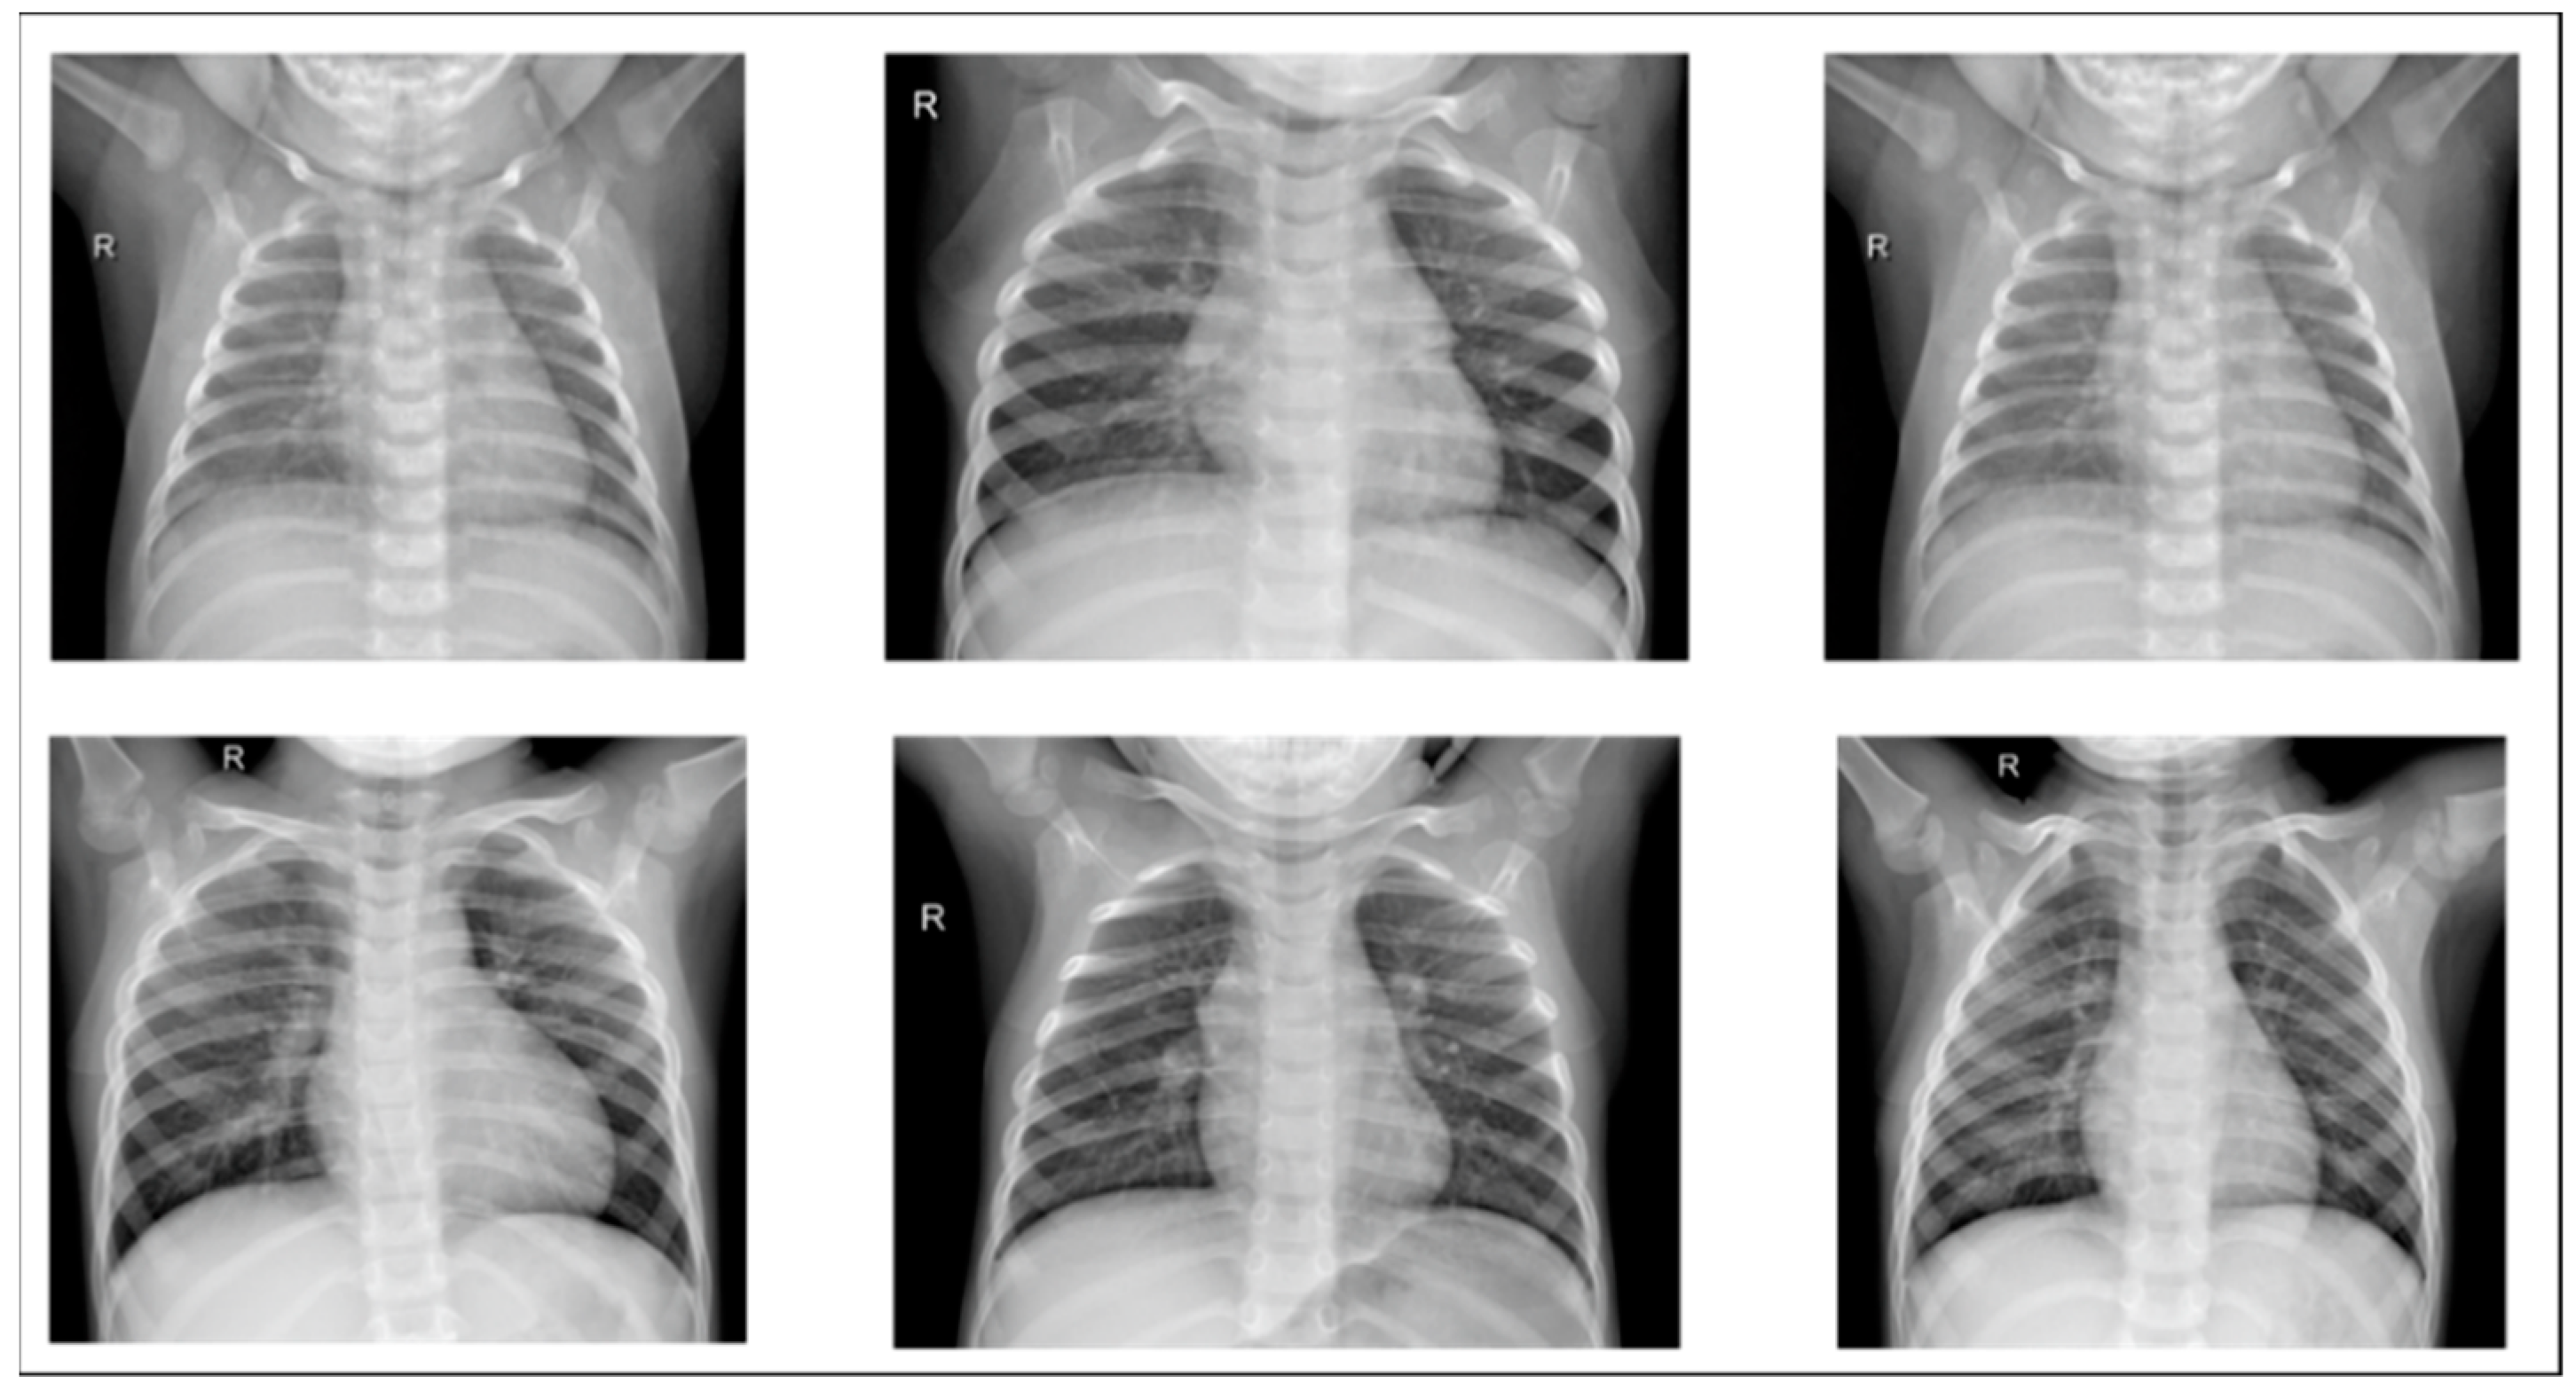

The study dataset included unbalanced positive and negative samples, with significantly fewer normal images than pneumonia images in both training and test sets and relatively low data volume. This could lead to poor post-training validation and overfitting. Therefore, we applied data augmentation on the original datasets, creating new images by horizontal flipping, rotating, scaling size and ratio, and changing brightness and color temperature for the original images to compensate for the lack of data volume. Data augmentation increased the training set from 5216 to 22,146 images, and the test set from 624 to 1000 images. Furthermore, some images were transferred from the training to test set for data balance and to ensure images in the test set were predominantly originals. Figure 11 and Figure 12 show examples of original and augmented images, respectively.

Figure 12. Example images after data augmentation.